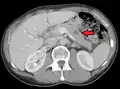

Metastases from the lungs to the pancreas